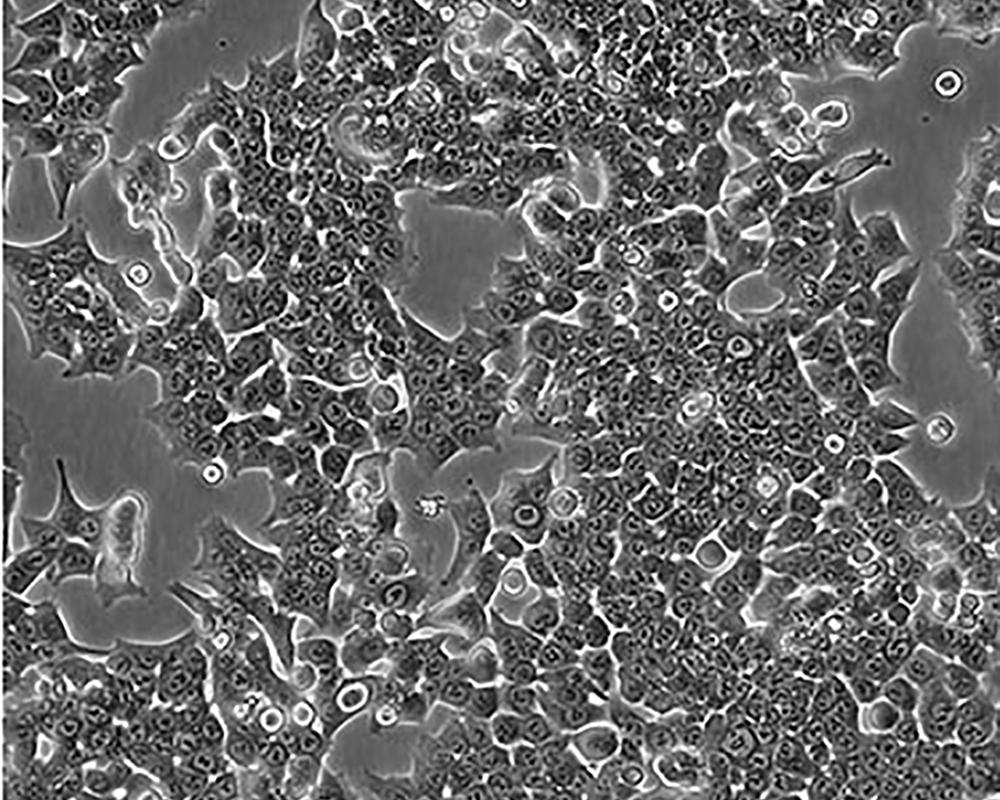

HCT 116

產(chǎn)品名稱 HCT 116

中文名稱 人結(jié)直腸腺癌細胞

組織來源 結(jié)腸腺癌;男性

生長特性 adherent

形態(tài)特征 epithelial

細胞描述 The cells are positive for keratin by immunoperoxidase staining.HCT 116 cells are positive for transforming growth factor beta 1(TGF beta 1) and beta 2(TGF beta 2) expression.